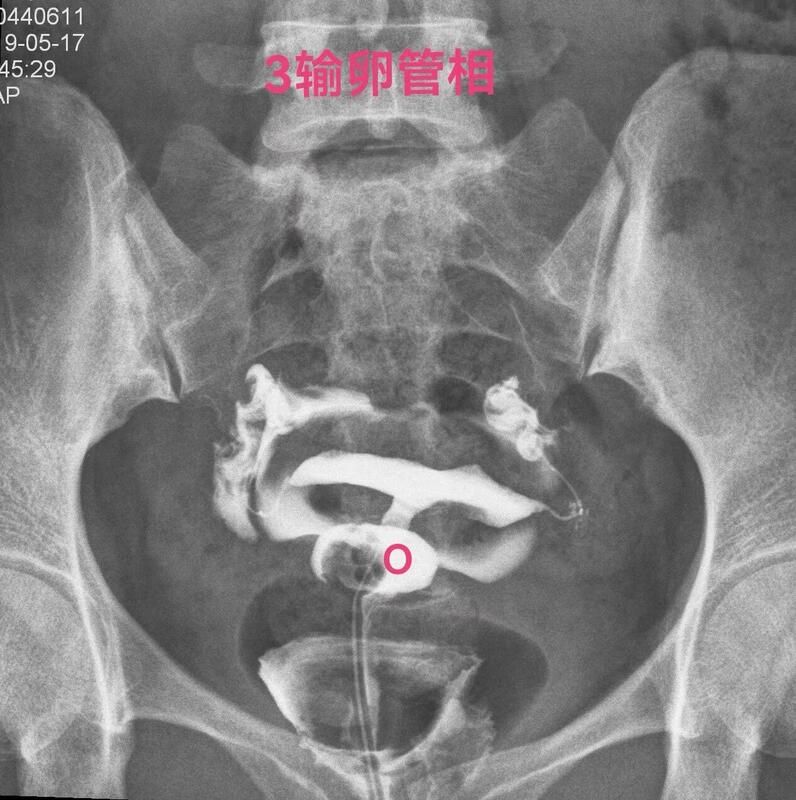

下面一例造影图就可以看直观看懂憩室导致经血流出不畅

2(1).jpg